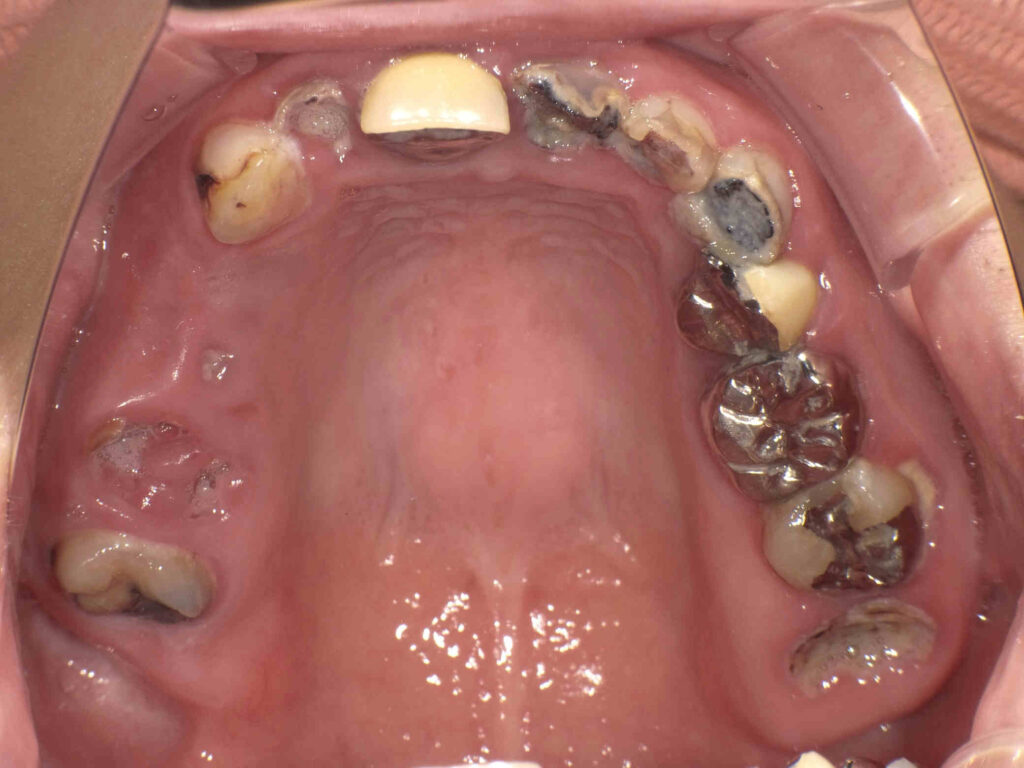

BEFORE

右上欠損部にはインプラントを計画。前歯は2本抜歯してグラデーションジルコニアブリッジ、左上はフルジルコニアとセレックを計画。

| 主訴 | 前歯を治したい。咬めない。 |

| 診断名・ 主な症状 |

右上臼歯部欠損による咀嚼障害及び、上顎前歯部う蝕による審美障害 |

| 年齢 | 40代女性 |

| 治療内容 | 右上:インプラントによるフルジルコニアブリッジとフルジルコニアクラウン (インプラントはGBR併用) 左上:フルジルコニアクラウンとセレックインレー (クラウンレングスニング併用) 前歯:グラデーションジルコニアブリッジ |

| 抜歯部位 | 上顎左右1番、右上5,6番 |

| 治療期間/ 通院回数 |

1年/20回 |

| 費用 | 2,024,000円 |